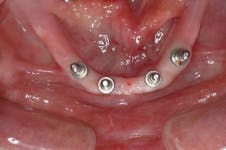

All-on-4 advocates claim that this type of treatment plan reduces cost and saves treatment time, but with the introduction of the ScrewIndirect one-piece implant that provides the implant, abutment, comfort cap, and transfer at a fraction of the cost of the implant alone from all the major implant companies, the economics argument for using the minimum number of implants is no longer valid. The ScrewIndirect screw-receiving platform allows splinting of implants that have up to 40 degree divergence, allowing distal angulations of up to 20 degrees if desired. Placement of five implants in the lower symphysis and six anterior to the maxillary sinuses can be relatively straight and still support adequate length of distal cantilevers. Four ScrewIndirect implants can also be placed, as shown below, splinted with a distal attachment for retention of an overdenture, but providing the patient with a fixed-detachable prosthesis that eliminates the need for a removable prosthesis is a more natural solution to restoring an edentulous jaw.

The ScrewIndirect one-piece implant offers a 3.0 mm D implant with adequate strength. All four diameter options (3.0 mm, 3.7 mm, 4.7 mm and 5.7 mm) have the same 5 mm D multi-unit platform. The 3.0 mm D implant allows treatment of narrow ridges and simplifies accurate placement during flapless surgery. Providing teeth in one day to edentulous patients and immediate implant placement following extractions is becoming the treatment of choice. The patient's existing denture is converted to a fixed-detachable prosthesis immediately following implant placement. This is accomplished by attaching titanium sleeves to the implants that project through holes cut in the denture and attached them to the denture with cold-cure acrylic followed by shortening the denture flanges.